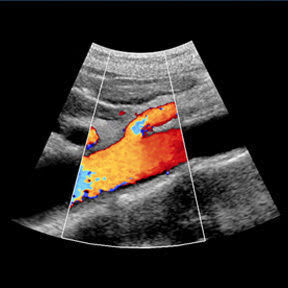

Vascular Screening

We recommend a vascular MOT for patient's over the age of 50. You check your teeth, your eyes, why not your veins & arteries too.